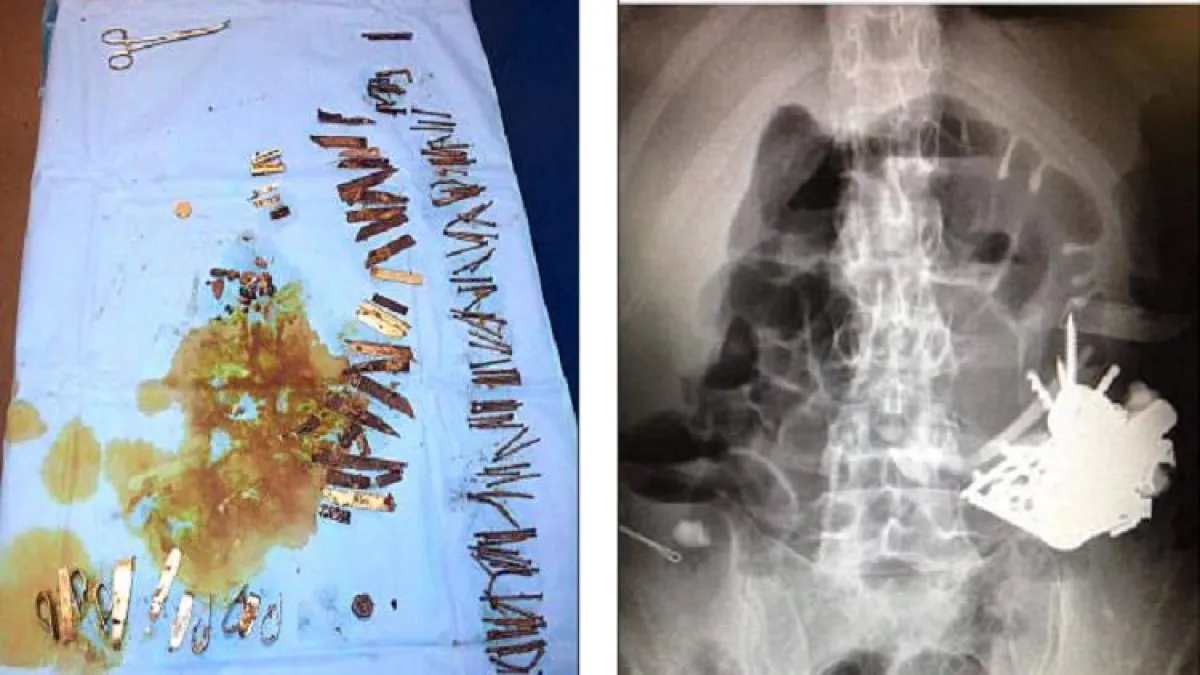

خضع رجل فرنسي لعمليات جراحية من أجل إزالة عشرات القطع المعدنية الموجودة في معدته، بما فيها أدوات حادة، بعد بقائها سنوات طويلة في معدته ، وبدأت بإحداث ثقوب ، في جهازه الهضمي.

وقضى الرجل الخمسيني سنوات عدة في ابتلاع الأدوات والقطع المعدنية، بسبب اضطرابه النفسي. ، حيث تجمعت القطع المعدنية معًا داخل جسده، وشكلت كتل تسمى "البازهر" (وهي أجسام غير قابلة للهضم).

وتم نقل المريض إلى الطوارئ مرات عدة، وخضع لـعمليات على مدى 5 سنوات، لأنه كان يتقيّأ دمًا ويتعرض لألم شديد، نتيجة وجود هذه الكتل في بطنه. وأُجريت له خمس عمليات لإزالة المسامير والسكاكين، والمكسرات، ورأس مفك البراغي، بالإضافة إلى مقابض المعالق والحصى، وأسلاك الحديد والعملات المعدنية، من بطنه.

وعلى الرغم من تلقّي المريض العلاج النفسي، إلا أنه استمر في ابتلاع الأشياء غير الصالحة للأكل على مدى سنوات عدة.